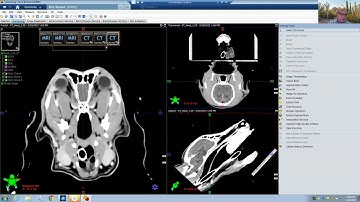

Varian Eclipse Contouring Basics